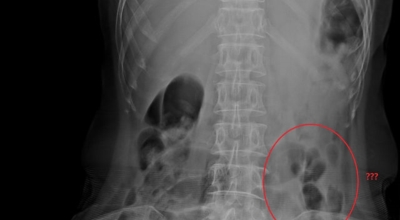

왼쪽 옆구리 통증 - 신장 결석증(신장 결석)

일반적으로 신장 결석으로 이름 난 신장결석증은 왼쪽 옆구리 통증의 일반적인 원인입니다. 이러한 결석은 대부분이 신장 골반 또는 종아리 내에서 형성되며 종종 요로를 막을 때 극심한 통증을 유발합니다. 그 결과 통증은 본질적으로 복통이며 왼쪽 옆구리에서 사타구니와 허벅지 안쪽으로 퍼집니다.